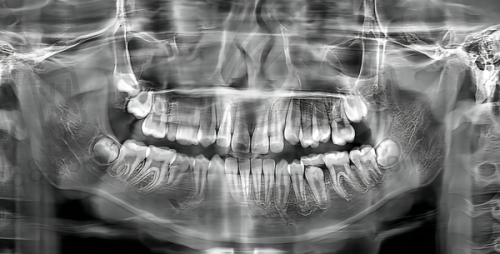

此外,私立口腔在设备和技术的引进上更加灵活。洪志口腔不断更新精良的口腔诊疗设备,如数字化口腔扫描仪、口腔CBCT等,这些设备能够更精细地诊断口腔问题,为治疗提供有力的支持。同时,诊所还积极引进国内外精良的口腔治疗技术,确保患者能够享受到良好质的口腔医疗服务。

即刻种植牙是洪志口腔的一项特色推荐项目。对于牙齿缺失的患者来说,传统的种植牙方式需要等待较长的时间,给患者的生活和饮食带来诸多不便。而即刻种植牙技术则可以在拔牙后立即植入种植体,大大缩短了治疗周期。

在洪志口腔,医生会在拔牙后对患者的牙槽骨进行评估,根据患者的具体情况制定个性化的即刻种植方案。医生们拥有丰富的临床经验,能够熟练操作即刻种植牙技术,确保种植体的稳定性和成功几率。术后,患者修复快,能够更快地修复正常的咀嚼功能和美观。

牙齿缺失修复也是洪志口腔的重点推荐项目之一。牙齿缺失不仅会影响美观,还会影响咀嚼功能和口腔健康。洪志口腔提供多种牙齿缺失修复方式,如烤瓷牙、全瓷牙、活动假牙等。医生会根据患者的口腔情况、经济状况和个人需求,为患者推荐更适合的修复方案。

对于烤瓷牙和全瓷牙修复,洪志口腔采用高品质的材料,确保修复后的牙齿美观自然,与真牙无异。在制作过程中,医生会严格把控每一个环节,确保修复体的质量和舒适度。而活动假牙则适合一些不适合种植牙或烤瓷牙修复的患者,洪志口腔的活动假牙佩戴舒适,稳定性好,能够有效修复患者的咀嚼功能。